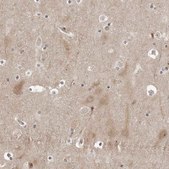

immunoblotting: 0.04-0.4 μg/mL

immunohistochemistry: 1:50-1:200

All Prestige Antibodies Powered by Atlas Antibodies are developed and validated by the Human Protein Atlas (HPA) project and as a result, are supported by the most extensive characterization in the industry.

The Human Protein Atlas project can be subdivided into three efforts: Human Tissue Atlas, Cancer Atlas, and Human Cell Atlas. The antibodies that have been generated in support of the Tissue and Cancer Atlas projects have been tested by immunohistochemistry against hundreds of normal and disease tissues and through the recent efforts of the Human Cell Atlas project, many have been characterized by immunofluorescence to map the human proteome not only at the tissue level but now at the subcellular level. These images and the collection of this vast data set can be viewed on the Human Protein Atlas (HPA) site by clicking on the Image Gallery link. We also provide Prestige Antibodies® protocols and other useful information.